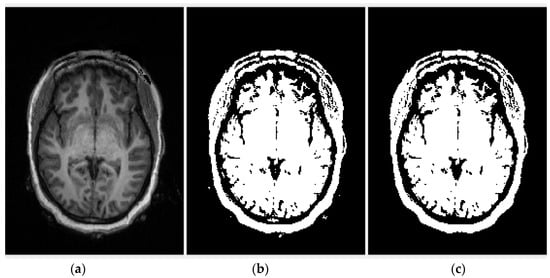

Area opening is equivalently defined as the union of all the morphological opening (erosion followed by dilation) with the connected structuring element of which the size is equal to η. Then, a rectangular area is achieved by searching for the first and last nonzero pixels along the rows (top and bottom) and columns (left and right) of the noise-free binary image, as shown in Figure 2.

Figure 2.

Steps for noise removal and region of interest (ROI) extraction.

Some of the ROI pixels inside the rectangular boundary (image I3) have value 0. To make all the ROI pixels in the image I3 to one, the complement of noise-free binary image I2 is multiplied (logical AND) with the rectangular boundary, such that all the pixels inside the boundary are equal to 1 (Figure 3a). Largest connected component (LCC) is chosen (Figure 3b) from the resulted image and added (logical OR) to I3 (Figure 3c). Lastly, morphological flood-fill operation [45] (p. 208) is used to fill the holes (0-valued pixels) and achieved the binary image I4 with a single ROI. This image is exploited as an input for PCA (Figure 3d).

Figure 3.

Intermediate steps between images I3 and I4, (a) logical AND of I2 with the rectangular boundary, (b) largest connected component, (c) logical OR of (b) with I3, (d) holes filling using morphological flood-fill operation.